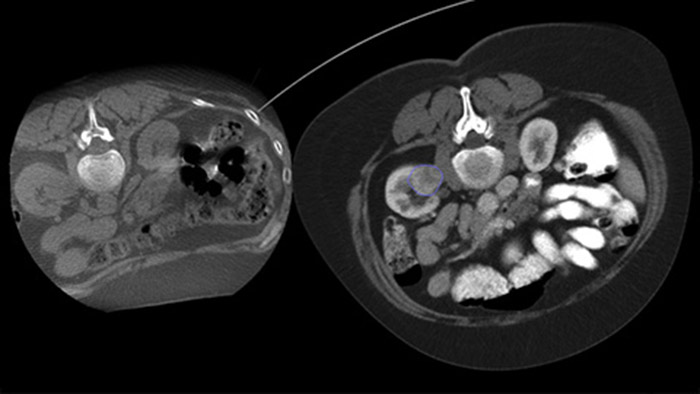

Dual View permite la superposición de una imagen 3D previa al procedimiento (TC/RM/PET) sobre una CBCT Dual 3D intraprocedimiento para visualizar mejor las lesiones y acceder a información crítica para la planificación de la trayectoria de la aguja.

Adquiera una CBCT posterior a la ablación para demostrar la extensión de la cobertura del tumor y confirmar la finalización de su tratamiento.